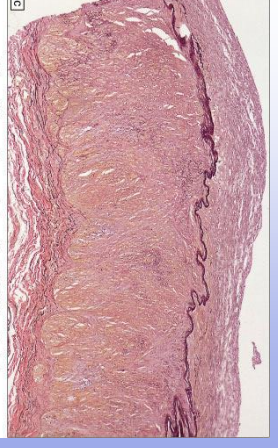

Fibromuscular Dysplasia: hyperplasia of smooth muscle and fibrous tissue alternating with thin, fibrotic regions; at risk for developing occlusions, dissection, aneurysm